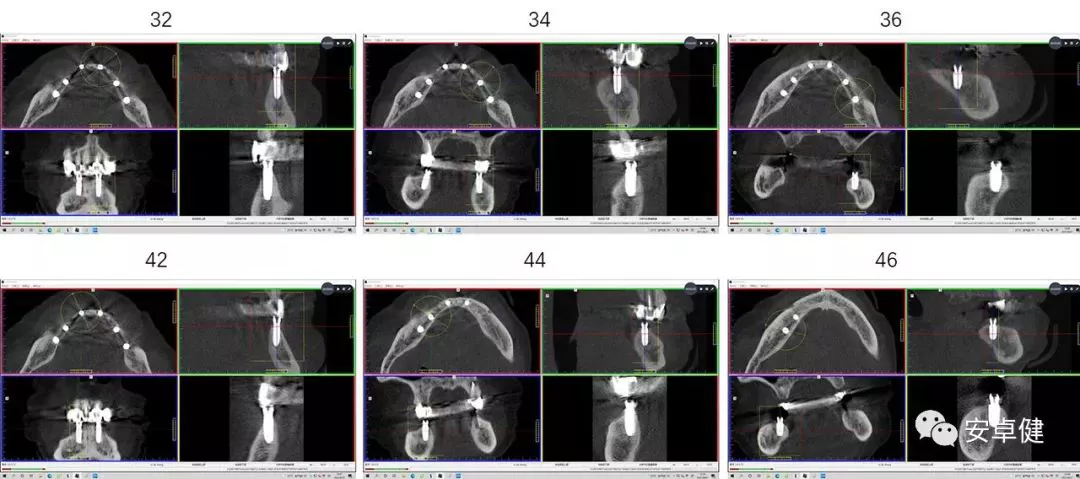

• Anthogyr Axiom® BL REG Φ3.4mm×12mm (32位点植入);

• Anthogyr Axiom® BL REG 3.4mm×10mm (42位点植入);

• Anthogyr Axiom® BL REG 4.6mm×8mm (36位点植入、46位点植入);

• Anthogyr Axiom® BL REG 4.0mm×10mm (34位点植入、44位点植入);

术后即刻CBCT示种植体三维植入位置良好,唇舌侧骨板可

二期复诊CBCT影像学检查示种植体周围骨密度良好,骨量可

种植两年后复诊CBCT影像学检查示种植体周围骨密度良好